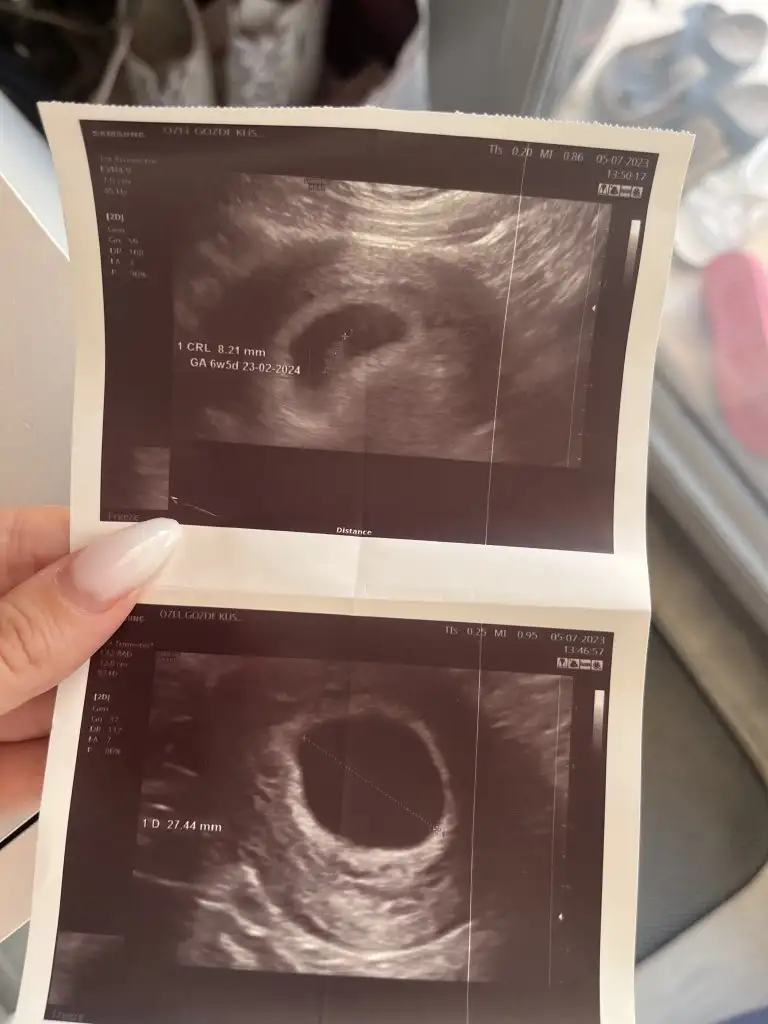

kalbini gördük pıt pıt atıyor pirinçten büyük boyu

kalbini gördük pıt pıt atıyor pirinçten büyük boyu  her şey yolundaymış şükür

her şey yolundaymış şükür